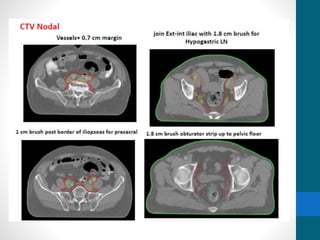

Contouring Vessels

• From L5 Lower border – femoral Head upper border

• CTV Nodal

• Vessels + 0.7mm margin

• Presacral 10mm brush

• Obturator 18mm

• CTV Nodal+CTV Primary = CTV Combined

• CTV Combined + 1cm = PTV

Contouring Vessels • FromL5 Lower border – femoral Head upper border • CTV Nodal • Vessels + 0.7mm margin • Presacral 10mm brush • Obturator 18mm • CTV Nodal+CTV Primary = CTV Combined • CTV Combined + 1cm = PTV